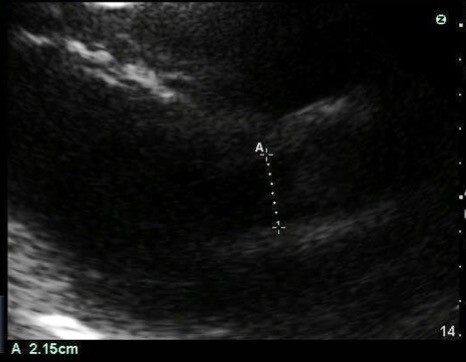

Cardiac 2 Stroke Volume Vasopressor Dependent Shock Example LVOT Image